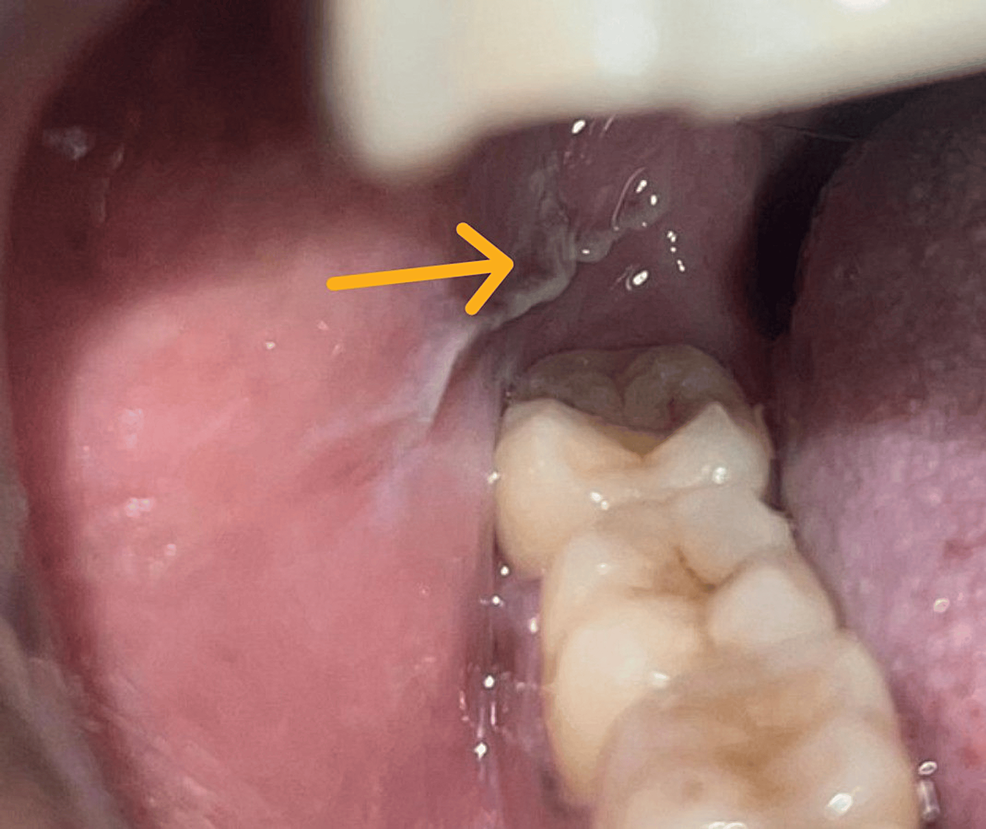

ضایعات ناشی از تروما یا تحریک

تحریک مکانیکی یا شیمیایی مداوم می تواند به بافت مخاط دهان آسیب برساند و ضایعات سفید ایجاد کند. این آسیب ها ممکن است به دلیل گاز گرفتن گونه، استفاده از پروتز نامتناسب، دندان تیز یا ترک خورده، یا مصرف مواد غذایی و نوشیدنی های بسیار داغ و تند رخ دهد.

ضایعات ناشی از تروما معمولا سطحی و محدود هستند و پس از حذف عامل محرک ظرف چند روز تا چند هفته بهبود می یابند. با این حال، اگر تحریک طولانی مدت ادامه پیدا کند، ممکن است تغییرات بافتی پایدار مانند کراتوز یا حتی لکوپلاکی ایجاد شود.

درمان در این موارد بسیار ساده ولی مهم است. باید عامل آسیب رسان مشخص و حذف شود، مثلا تراش دندان تیز یا تنظیم پروتز. در برخی موارد پزشک از دهان شویه های ضد التهاب یا ژل های محافظ برای کاهش درد و سرعت ترمیم استفاده می کند.